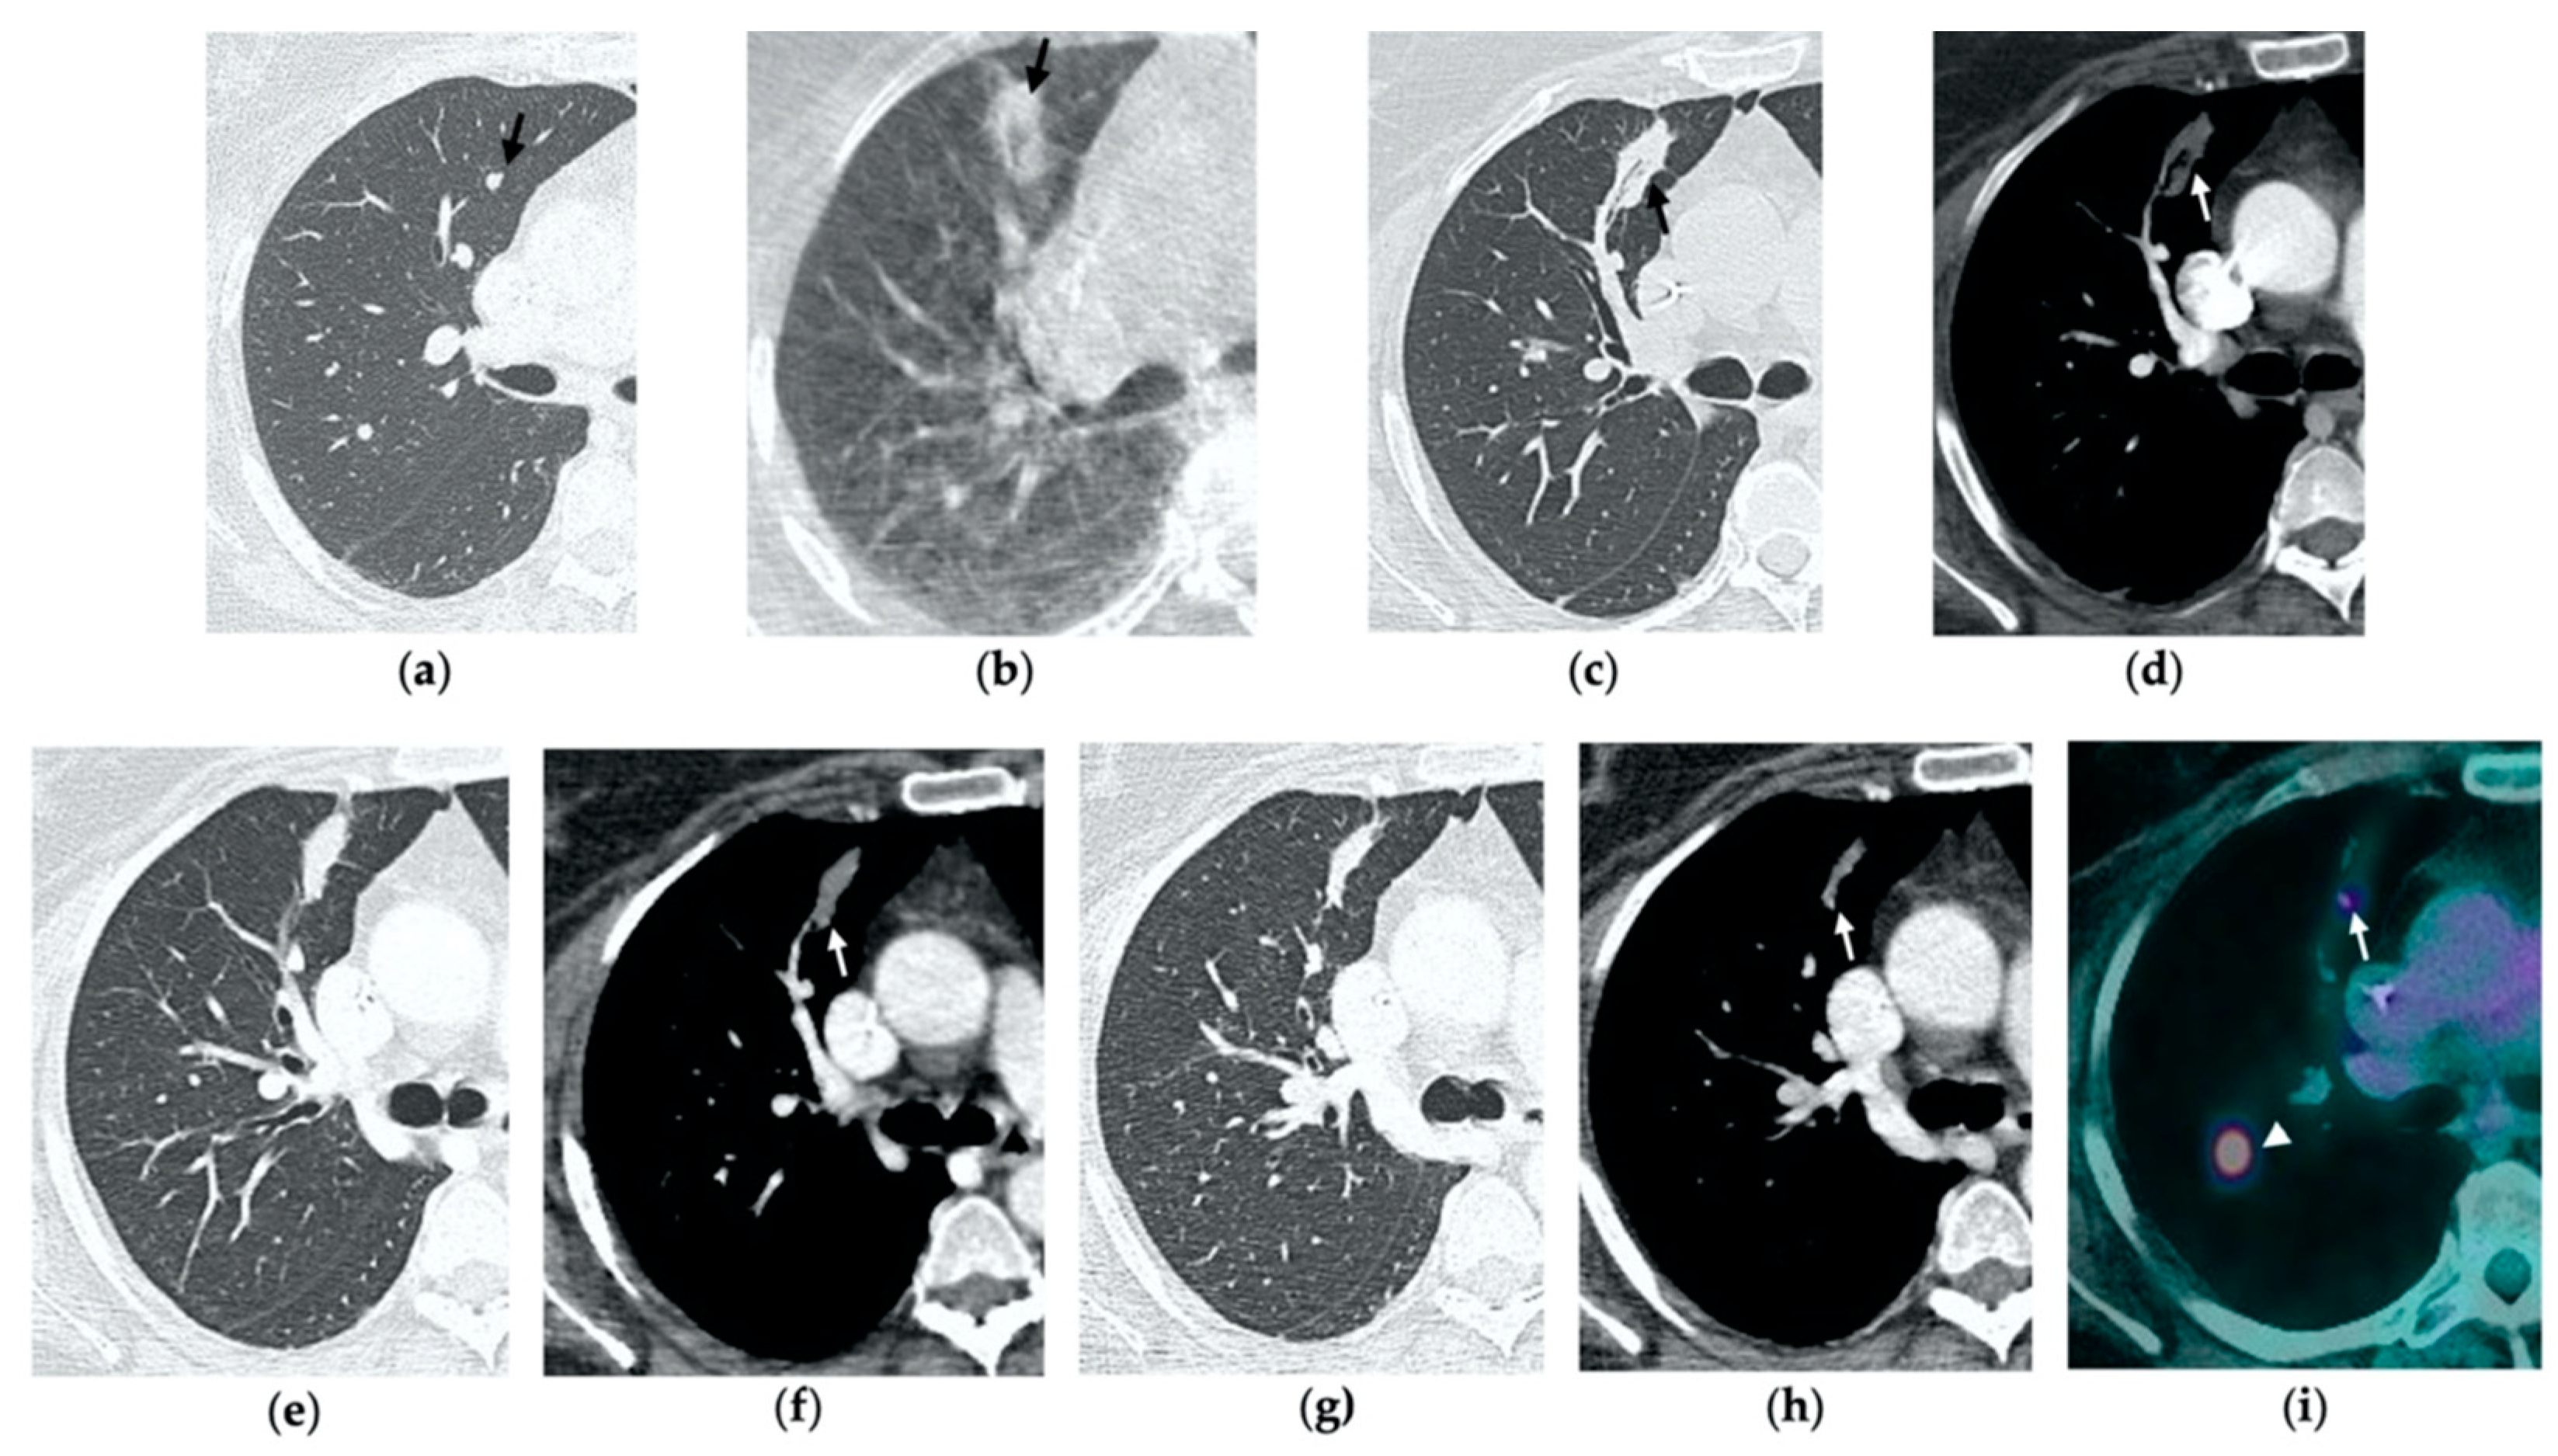

Figure 3. 63-year-old woman with pulmonary metastasis from colorectal cancer (CRC) in the right upper lobe. (a) Axial CT of the metastasis (black arrow) prior to treatment. (b) Cone-beam CT image obtained post-procedure shows hazy GGO (black arrow) of the ablation site surrounding the treated nodule. (c,d) Axial 2-month follow-up CT images show a large consolidation with hypoattenuating bubbles (black arrow) and no contrast uptake (white arrow). (e,f) Axial 5-month follow-up CT images demonstrate a decrease in the size of the consolidation (black arrow) with no central contrast enhancement (white arrow). (g,h) Axial CT images obtained after 8 months show minimal further decrease in size with no signs of residual disease.

Figure 4. 63-year-old-woman (same patient in Figure 3) with pulmonary metastasis from CRC in the right upper lobe. (a) Axial CT before treatment (black arrow). (b) Cone-beam CT image obtained at the end of the procedure shows GGO (black arrow) around the treated lesion. (c,d) Axial 2-month follow-up CT images show an elongated consolidation with hypoattenuating bubbles (black arrow) and no contrast uptake (white arrow). (e,f) Axial 5-month follow-up CT images demonstrate a tiny nodular uptake of contrast on the posterior margin of the consolidation (white arrow), suggestive of residual disease. (g,h) On axial CT images after 8 months the nodular enhancement persists (white arrow). (i) PET/CT image at 9 months proves residual disease on the treated lesion (white arrow) as well as simultaneous metastasis (white arrowhead) in the posterior segment.

4. Residual or Recurrent Disease

During follow-up, there are several evolution patterns of the ablation site, which should promptly raise the suspicion of incomplete ablation or local recurrence.

On post-procedural CBCT, if the tumor is not completely encircled by the GGO rim, there is a high probability of incomplete treatment.

At the 1-month follow-up, incomplete ablation should be suspected if there is no increase in size of the ablation zone or if the consolidation demonstrates nodular enhancement akin to the original tumor [7,8].

At 6 months, any growth in size of the ablation area is suggestive of recurrence [7].

At all stages of follow-up, the appearance of either central or peripheral nodular or irregular enhancement should be considered as residual or recurrent disease (Figure 4f and Figure 5f), since the ablated area undergoes fibrous transformation, and it should not show contrast enhancement, except for the persisting peripheral safe zone [7,15].